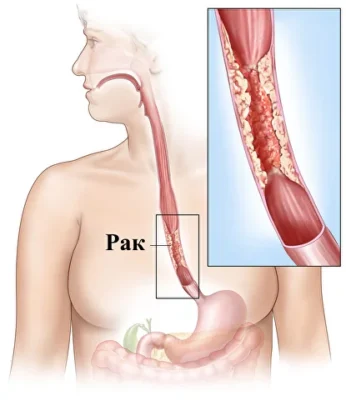

食管癌是一种恶性肿瘤。其发生源于食管黏膜细胞的异常突变,随着时间的推移,疾病不仅会扩散至食管壁的各个层次,还会沿着食管蔓延。肿瘤逐渐阻塞食管腔,阻碍食物通过,导致患者出现消瘦,严重时甚至死亡。

食管癌的类型

- 胸段食管癌.

- 食管下三分之一部位癌.

- 颈段食管癌.